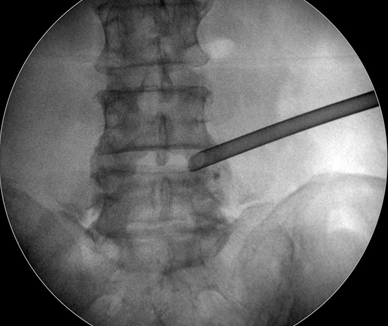

椎間孔鏡微創(chuàng)手術(shù)全程在影像導(dǎo)航引導(dǎo)下進(jìn)行,定位精確;針孔將突出髓核消融和取出,達(dá)到與開放性手術(shù)同樣的目的;不再大動干戈、傷筋動骨。杜醫(yī)師介紹,該微創(chuàng)療法,手術(shù)目標(biāo)性強(qiáng)、不融合間隙、手術(shù)部位的創(chuàng)傷小、恢復(fù)快、相關(guān)并發(fā)癥少,術(shù)后病患即可下地活動,相對減輕了專職護(hù)理人員和家屬的術(shù)后護(hù)理壓力和負(fù)擔(dān)。